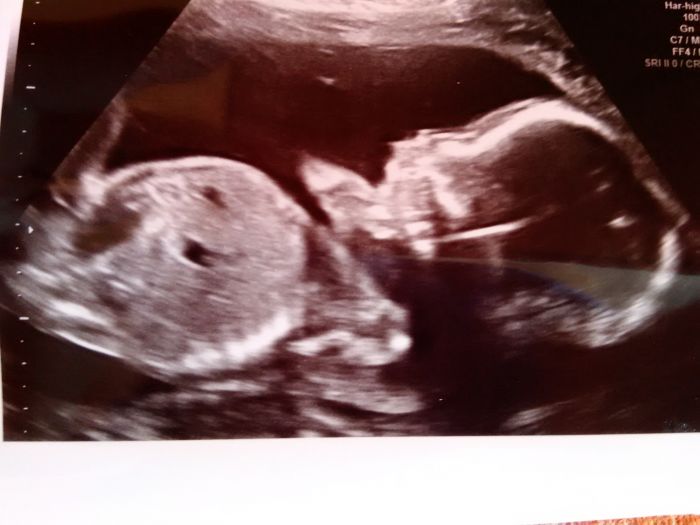

My včera byli na velkém UTZ. a vše co ma mít ma a náležitě funguje akorát ma pindika s tím sem nepočítala, ale hlavne ze je zdravej a ma 360 g .Tatínek je pyšný a mel radost za vsechny 3

Přikládám foto ze včerejška 20+4 krycí jméno John